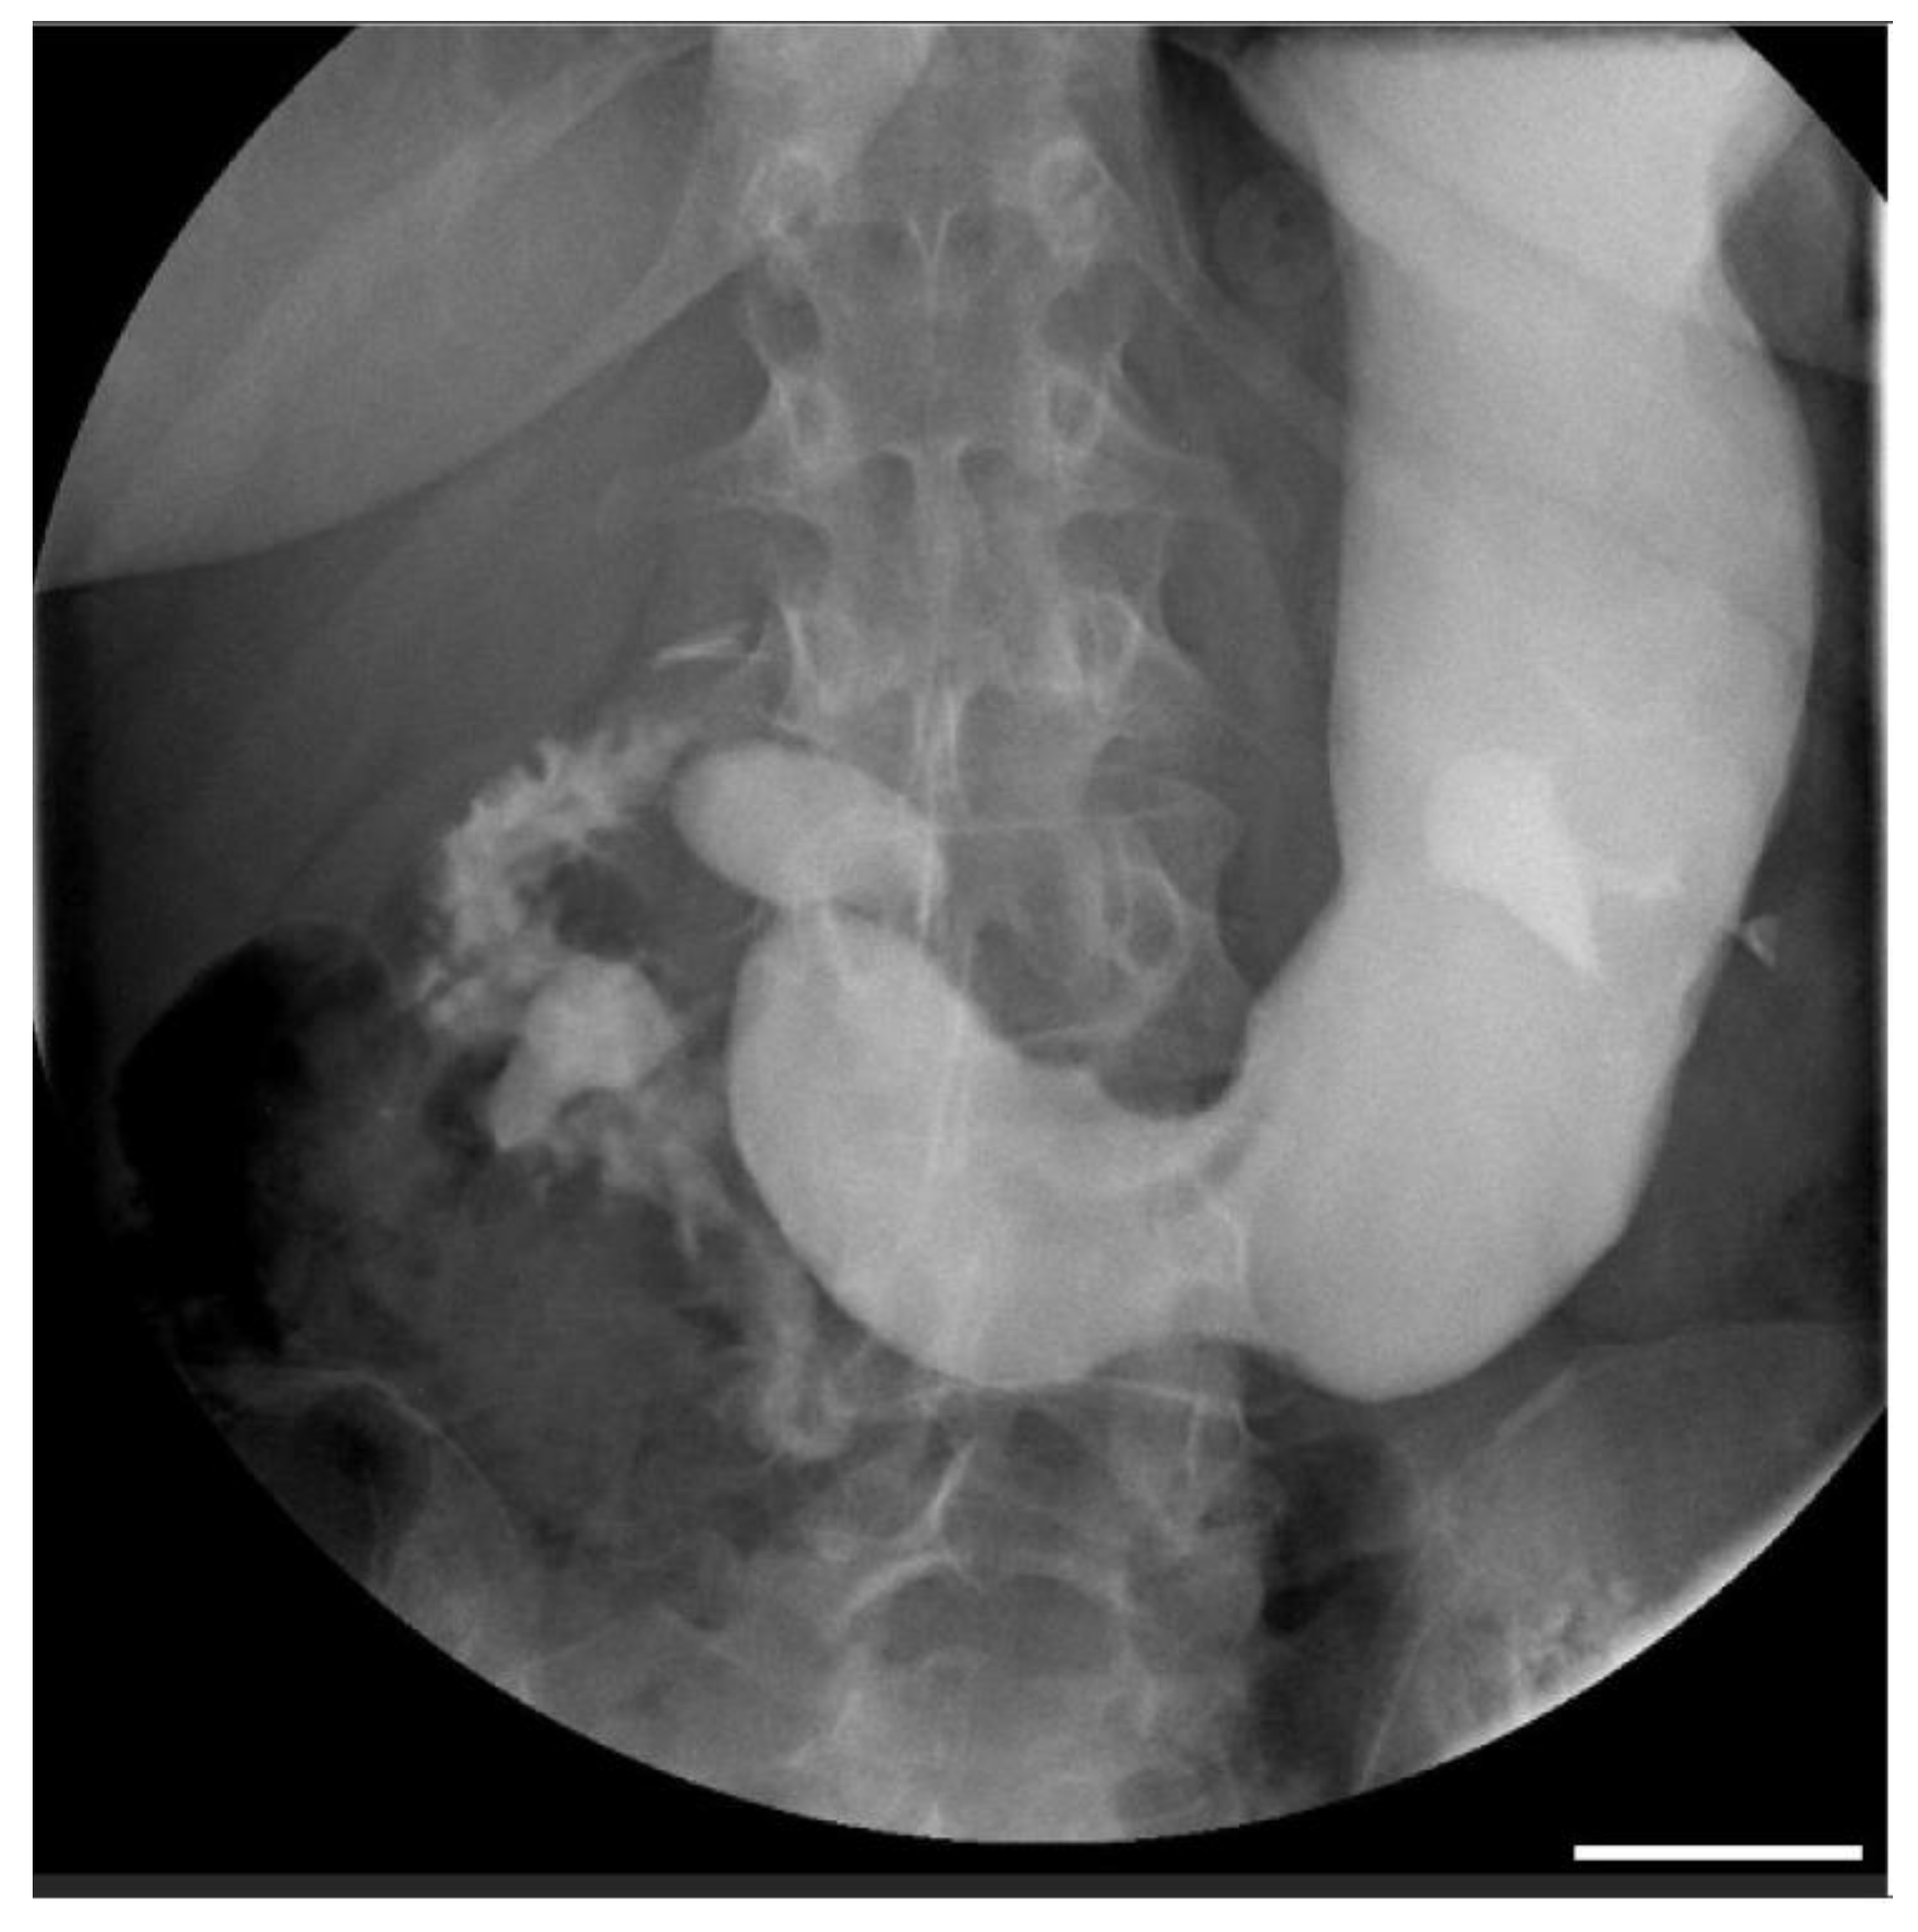

| Wang et al., 2021 [21] | 15-year-old male | Hematuria, fatigue, anorexia, nausea, and recurrent abdominal distension | Doppler US Upper GI gastrografin | Pulse dose of methylprednisolone 500 mg daily for 3 days, followed by 1 mg/kg orally and mycophenolate mofetil 0.75 g twice a day |